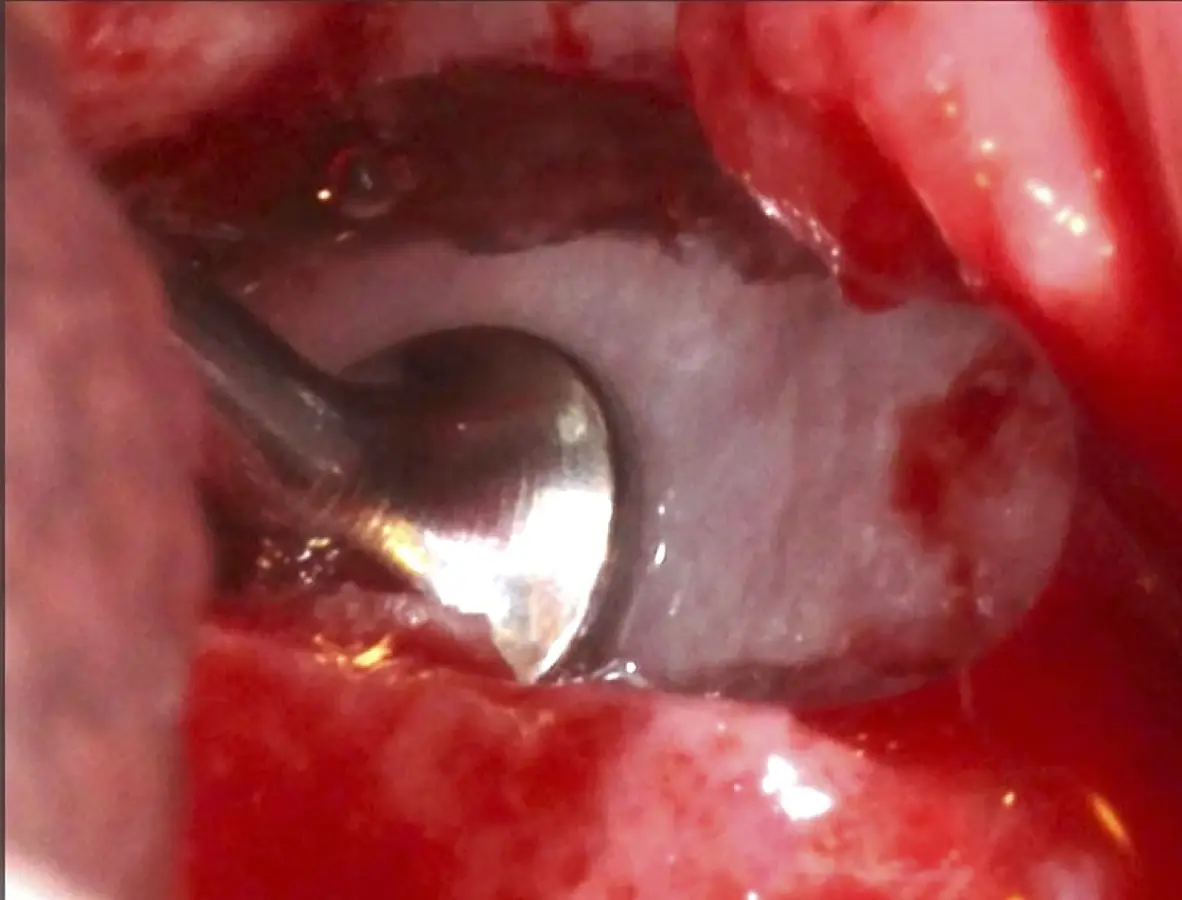

Se inicia la elevación de la membrana de Schneider con el inserto redondeado no cortante en forma de disco, empleando movimientos suaves. El levantamiento puede complementarse con elevadores convencionales, siguiendo la dirección mesiodistal. La fase de desprendimiento inicia con el piso y sigue hacia la pared mesial para terminar, y de ser necesario, hacia la pared posterior. Existen diversos insertos con angulaciones y longitudes para mayor accesibilidad16 (Figura 1).

Figura 6. Técnica por retiro de la tabla ósea. Una vez retirada o fracturada la tabla ósea, se introduce el inserto de presión hidráulica entre la membrana de Schneider y los bordes de la ventana, con suaves movimientos se inicia el desprendimiento gracias al chorro de agua expulsado a través del inserto (Figura 7).

Inserto de presión hidráulica iniciando el desprendimiento de la membrana de Schneider (a, b ).

Figura 7. Inserto de presión hidráulica iniciando el desprendimiento de la membrana de Schneider (a, b ).

Figura 17. Inicio del desprendimiento de la membrana de Schneider con el inserto de presión hidráulica.